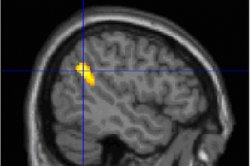

Почему почти никто не запоминает свои сныФранцузские ученые обнаружили, что у людей, которые хорошо помнят свои сны, в коре мозга есть две области повышенной активности, которые работают как во сне, так и наяву. Исследование опубликовано в журнале Neuropsychopharmacology, кратко о нем пишет Inserm. В ходе исследования нейробиологи составили две группы добровольцев. В одну из них ...